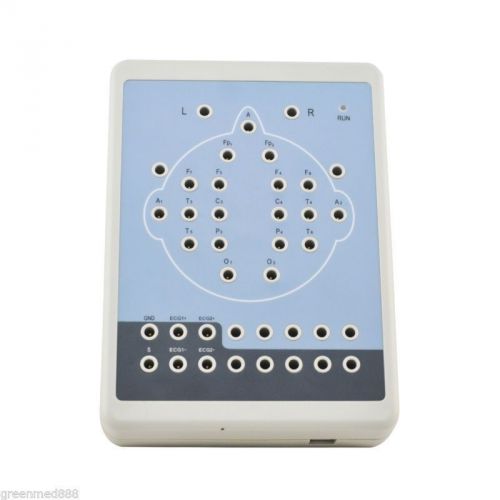

CE CONTEC Digital 16-Channel EEG and Mapping system+Tripod,KT88 1016 EEG MACHINE

CE FDA 16/18 Channel Digital EEG NeuroScape EEG-16 Machine Free CD Software TOP

16/18 Channel Digital EEG NeuroScape EEG-16 Machine +Free CD Software top